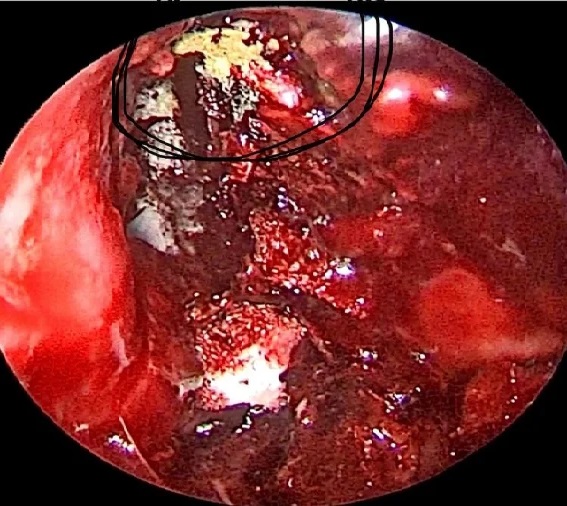

*ब्लैक-व्हाइट के बाद अब येलो फंगस ने दी दस्तक यहां मिला पहला मामला*

गाजियाबाद (शोर सन्देश)। कोरोना संक्रमण, ब्लैक फंगस और व्हाइट फंगस से अभी राहत भी नहीं मिली थी कि येलो फंगस नाम के नए खतरे ने दस्तक दे दी है। गाजियाबाद में येलो फंगस के पहले मरीज की पुष्टि हुई है। ब्लैक और व्हाइट फंगस के बाद अब गाजियाबाद के एक मरीज में येलो फंगस की पुष्टि हुई है। इलाज करने वाले डॉक्टर बीपी त्यागी ने बताया कि 45 वर्षीय मरीज पहले कोरोना संक्रमित हुए थे और वह डायबिटीज से भी पीड़ित हैं। ब्लैक फंगस का इलाज करने के लिए ओटी में सफाई चल रही थी, इसी दौरान जांच में पता चला कि मरीज येलो फंगस से भी संक्रमित हैं। फिलहाल मरीज की हालत में सुधार है। बताया गया कि इस बीमारी को म्यूकर स्पेक्टिक्स कहा जाता है। बता दें कि येलो फंगस के इस मामले ने डॉक्टरों की चिंता बढ़ा दी है। डॉक्टरों के अनुसार यह ब्लैक और व्हाइट फंगस से भी ज्यादा खतरनाक हो सकता है। यह इस हद तक खतरनाक हो सकता है कि मरीज के लिए जानलेवा भी साबित हो सकता है।डॉक्टर ने बताया कि अभी तक यह येलो फंगस छिपकली और गिरगिट जैसे जीवों में पाया जाता था। इतना ही नहीं, यह जिस रेपटाइल को यह फंगस होता है वह जिंदा नहीं बचता इसलिए इसे बेहद खतरनाक और जानलेवा माना जाता है। पहली बार किसी इंसान में यह फंगस मिला है।

डॉक्टर के अनुसार येलो फंगस गंदगी के कारण होता है। यह फंगस सामान्य रूप से जमीन पर पाया जाता है। छिपकली और गिरगिट जैसे जिस जीव की रोग निरोधक क्षमता कम होती है यह उसे असर करता है और कमजोर कर के जानलेवा तक बन जाता है। डॉक्टरों का अनुमान है कि कोरोना के कारण अब इंसानों की इम्युनिटी कमजोर हो रही है इसलिए यह फंगस उन्हें चपेट में ले रहा है।

00 येलो फंगस के लक्षण

- नाक का बंद होना।

- शरीर के अंगों का सुन्न होना।

- शरीर में टूटन होना और दर्द होना।

- शरीर में अत्यधिक कमजोरी होना।

- हार्ट रेट का बढ़ जाना।

- शरीर में घावों से मवाद बहना।

- शरीर कुपोषित सा दिखने लगना।